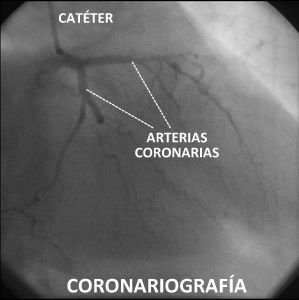

Si inyectamos contraste en las arterias coronarias (a esto se le llama “coronariografía”) podemos ver su interior, y comprobar si alguna arteria está obstruida. Si la obstrucción es importante se puede intentar arreglar gracias al cateterismo. Para ello se inflan una serie de balones y de muelles (llamados “stent”) dentro de la arteria coronaria para limpiar la obstrucción, y que la sangre pase de nuevo con normalidad. A veces las obstrucciones no se pueden solucionar con el cateterismo, y es preciso recurrir a la cirugía cardiaca (mediante la colocación de “puentes” o “by-pass”).